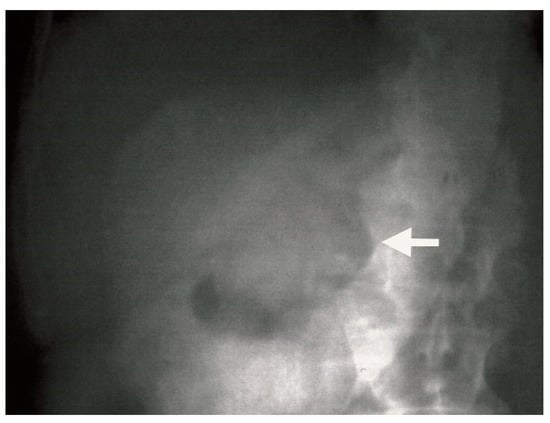

Ultrasound examination of the abdomen revealed a collapsed gallbladder with multiple gallstones of varying sizes, the largest measuring 4.2 cm. This raised concern for possible perforation of the gallbladder. Plain abdominal radiography revealed the presence of gas in the bile ducts, or aerobilia (Figure 6).

Figure 6.

Plain abdominal radiograph showing pneumobilia (white arrow) in the gallbladder.